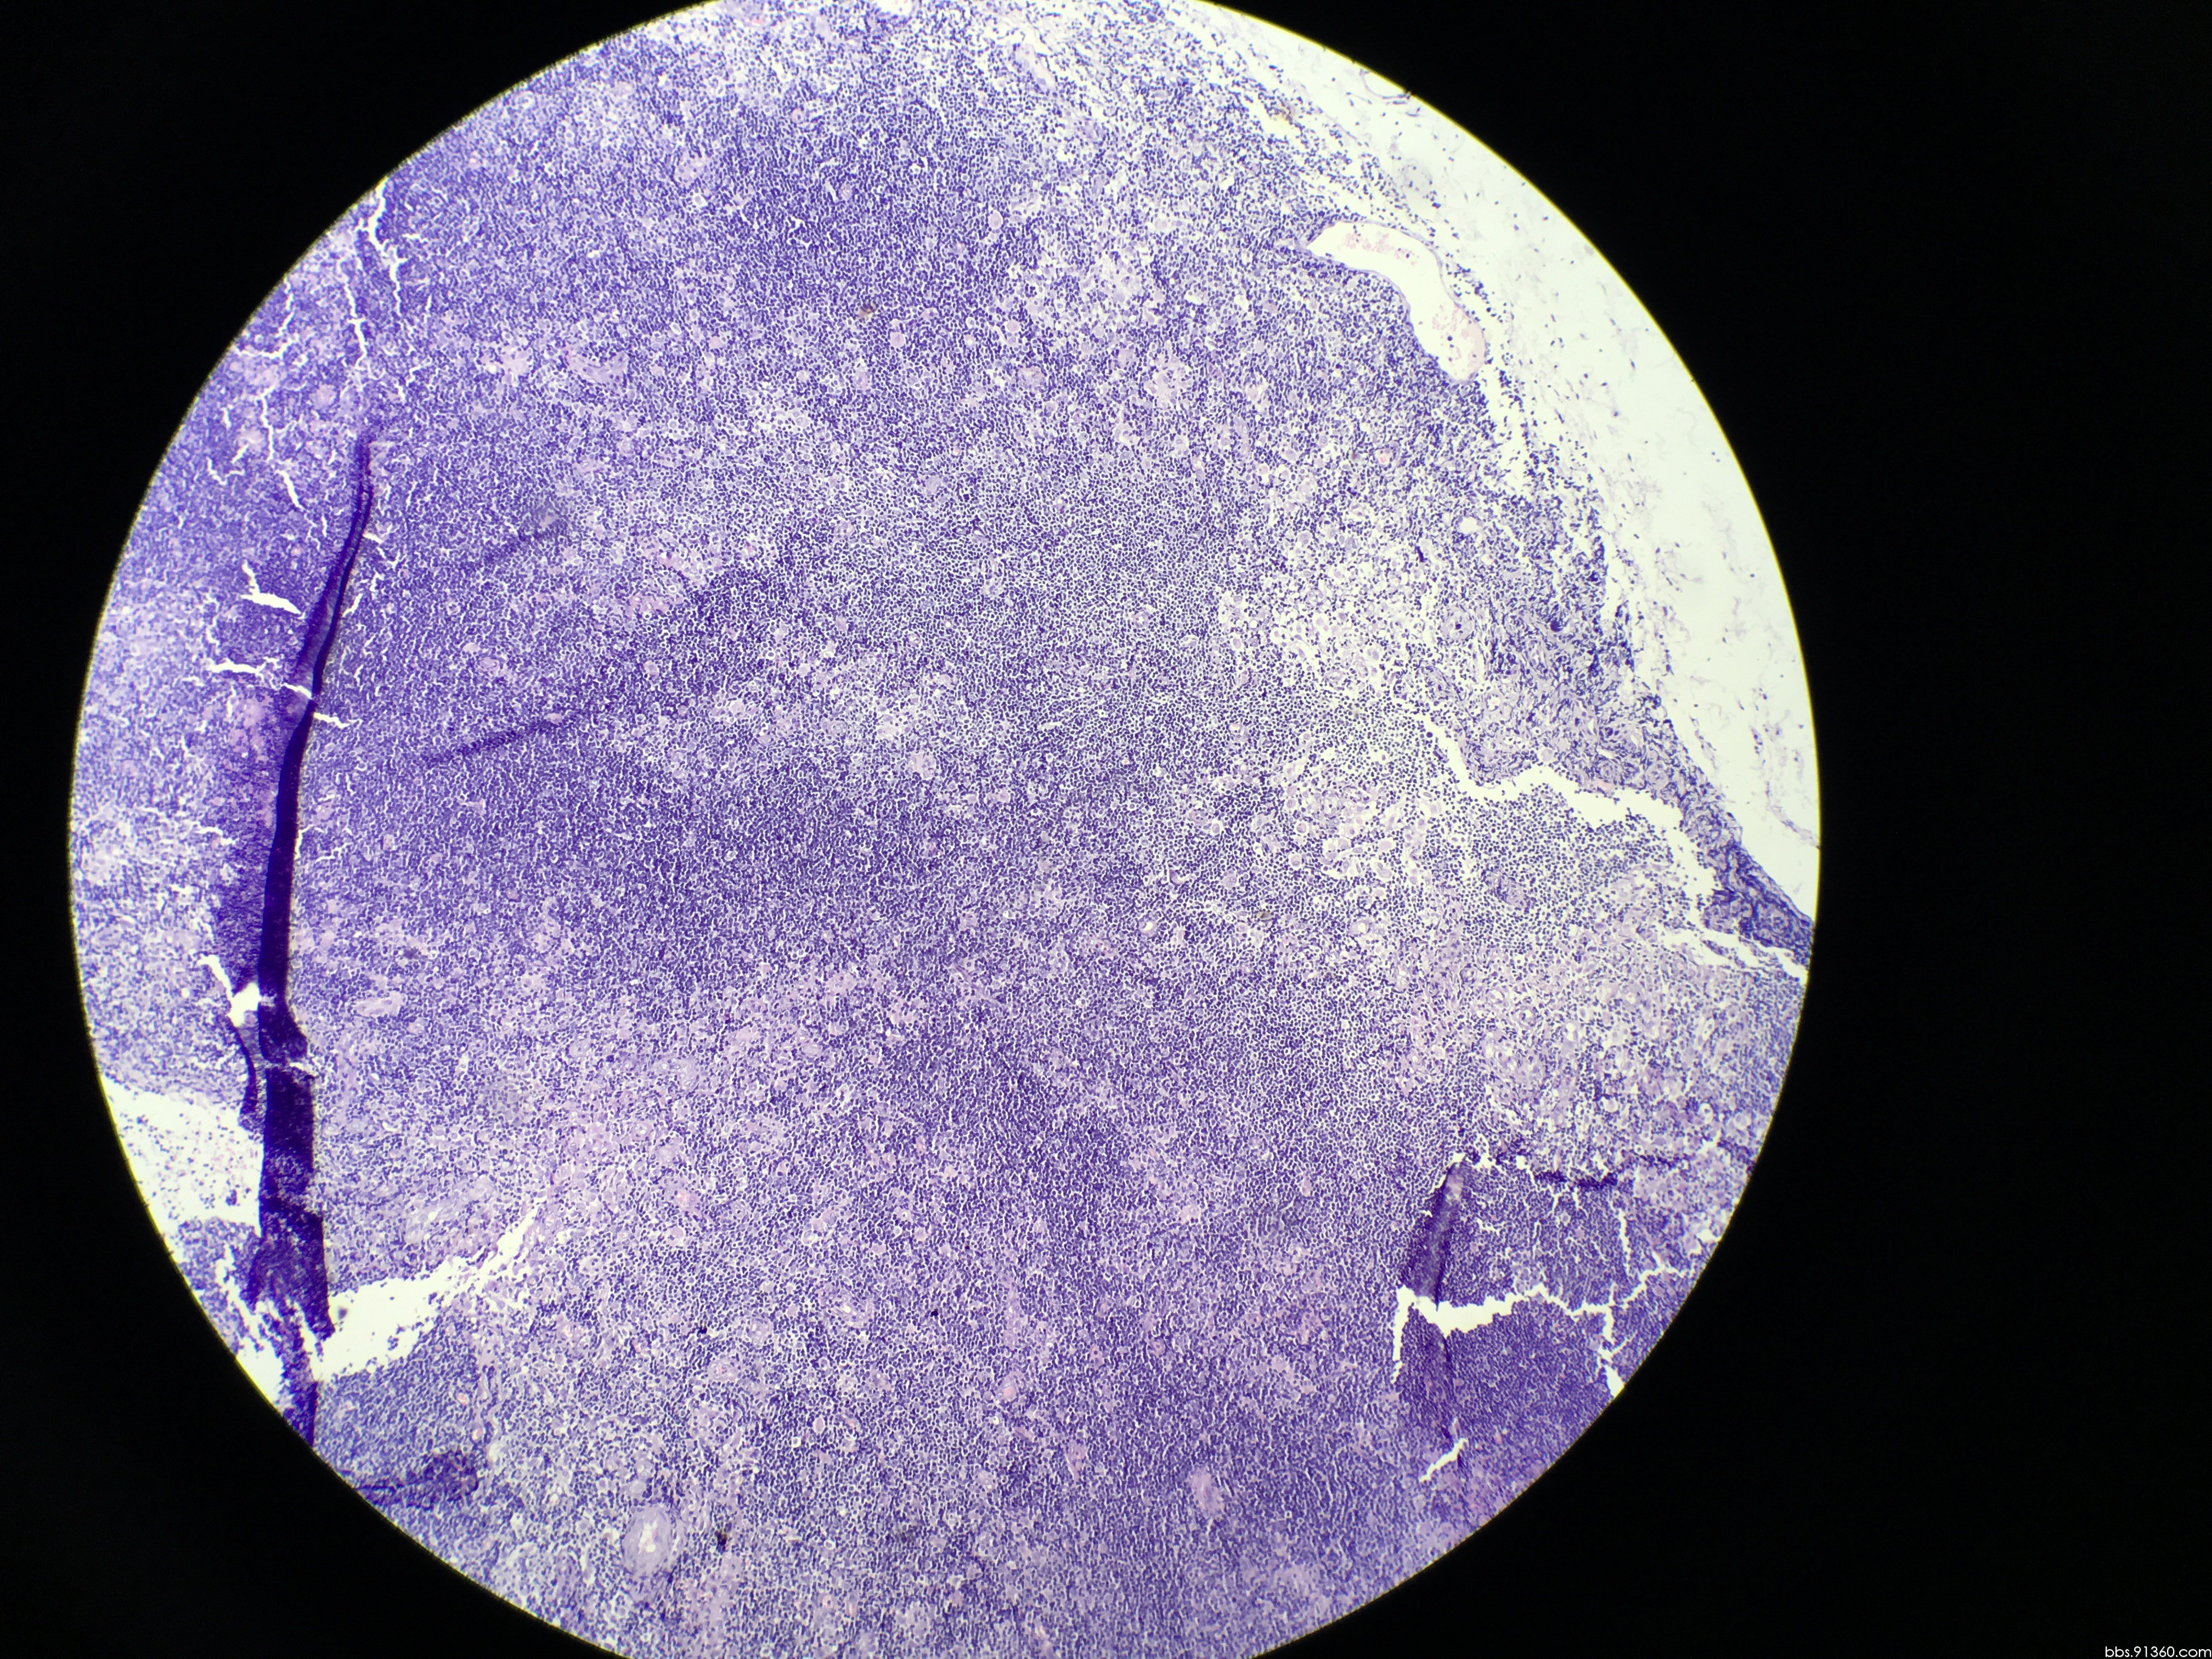

结膜肿物淋巴瘤?mikulicz综合征? [病例帖]

图片尺寸2448x3264